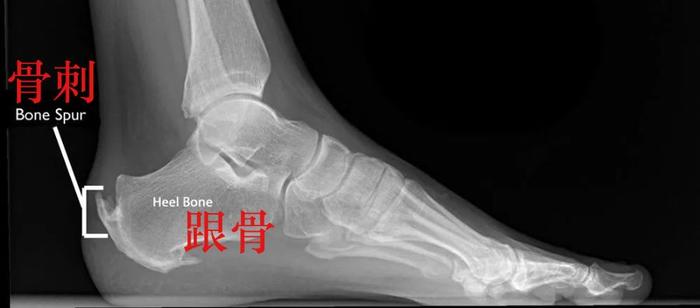

随之而来的是,跟腱附着点炎症病变,肌腱会出现钙化转变为骨质,也就是我们常说的“骨刺”。

骨刺

(photo via Bouldercentre for Orthopedics&Spine)